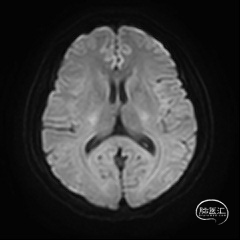

术后复查头部CT可见Surpass Streamline FD全程无狭窄,贴壁满意。患者无神经功能缺损表现,医嘱离院。